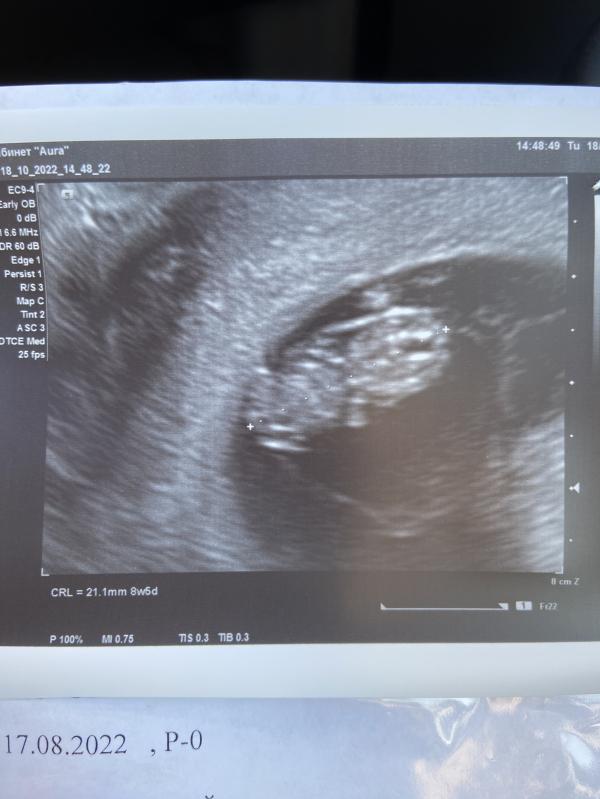

8 недель а уже прям человечка видно, я ходила первый раз на 7 недель, там прям малюсенькая креветочка была ☺️

Вот и я думала, что увижу малюсенькую точечку или вообще как пишут « размер вишни» 😁 а тут и ручки и ножки видно даже лицом к нам повернулся 😅 спасибо большое 🙏🏼💛 и тебе тоже хорошей и спокойной беременности 💕